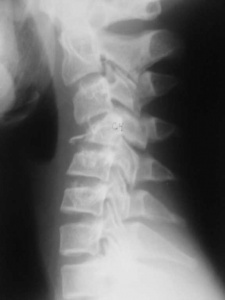

Локальный статус со стороны позвоночника: положение ребенка на каталке на спине, шейный отдел фиксирован головодержателем. Перед проведением осмотра пациент был вертикализирован, головодержатель снят. Визуально положение головы правильное. Нарушения целостности кожных покровов, отека, кровоподтеков в области волосистой части головы, лица, шейного и грудного отделов позвоночника нет. При пальпации позвоночника отмечалась болезненность по остистым отросткам, межостистым промежуткам, паравертебрально на протяжении среднего и нижнего шейного, верхнего грудного отделов. Осевая нагрузка на шейный отдел позвоночника умеренно болезненна. Сосудистых и неврологических расстройств в верхних конечностях не выявлено. По результатам рентгенографии шейного отдела позвоночника в боковой проекции диагностирована компрессия тел CIV, CV позвонков, оссификация атланто-окципитальной мембраны CI позвонка (рис. 1, а). По результатам МРТ-исследования шейного и грудного отделов позвоночника подтверждена компрессия тел CIV, CV позвонков и установлены компрессионные переломы тел ThIII, ThIV, ThV позвонков (рис. 1, б, в).

На основании жалоб, анамнеза, результатов клинической и лучевой диагностики выставлен диагноз: «Компрессионные неосложненные переломы тел CIV, CV, ThIII, ThIV, ThV позвонков. Ушиб волосистой части головы. Оссификация атланто-окципитальной мембраны CI позвонка».